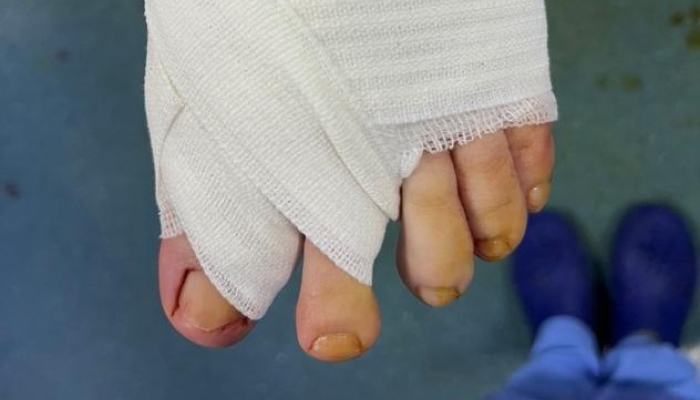

Pansement post opératoire